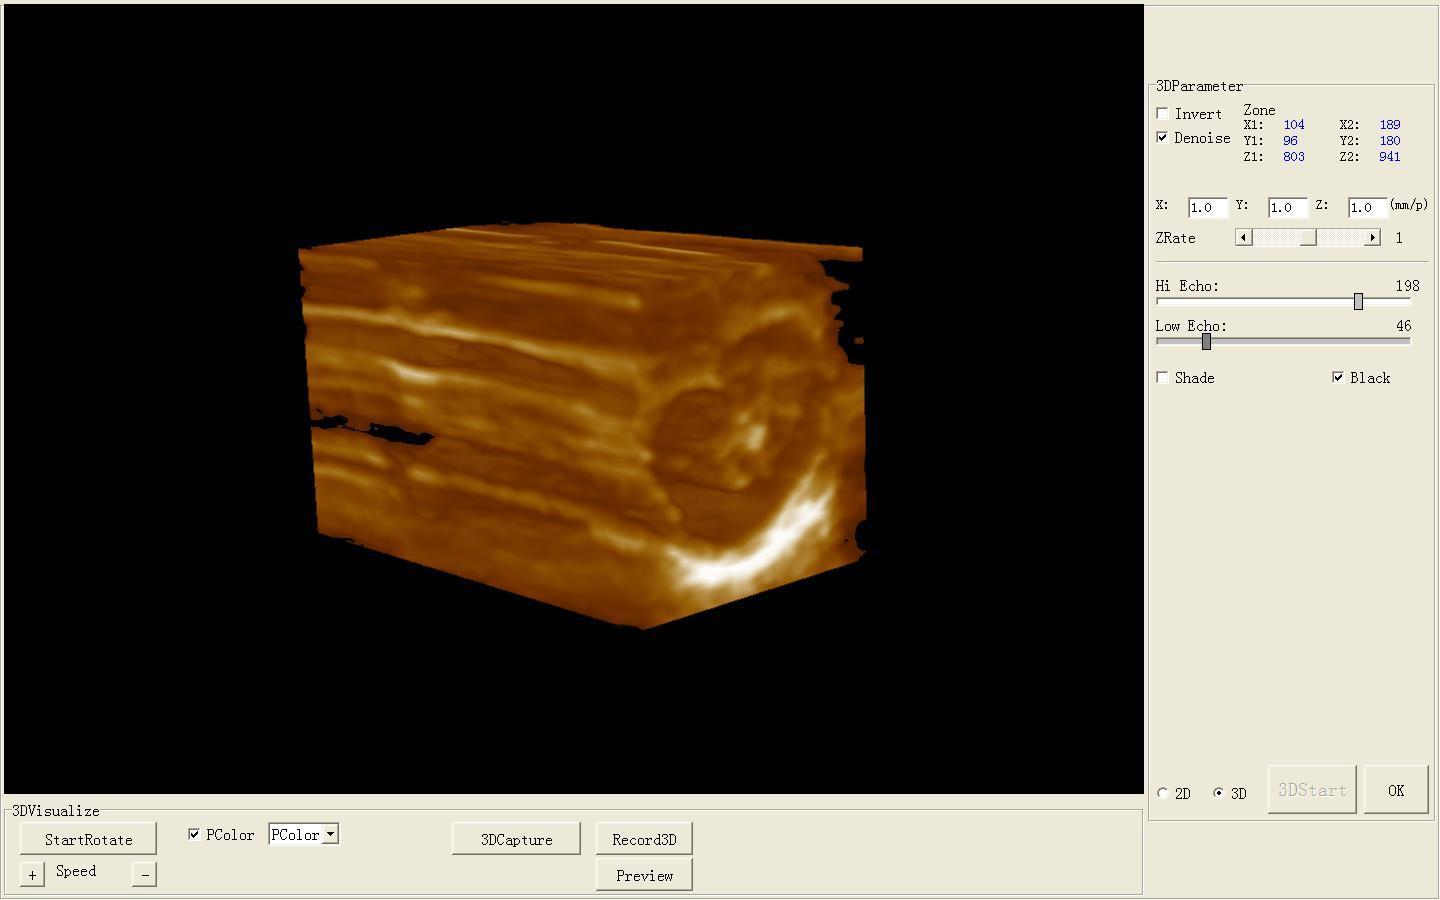

Ultrasound Scanner Machine 7.5Mhz Linear Probe Free 3D modul Vascular Scan Fast 190891351487

Ultrasound Scanner machine Rectal Probe 3D Laptop Machine Digital Veterinary AA 190891879431

Ultrasound Scanner Machine System Convex Linear Transvaginal 3 Probe 3D Software 190891518705

Ultrasound Scanner Machine Unit 3.5Mhz Convex Transvaginal Probe Free 3D CE

Ultrasound Scanner Machine with Micro-convex Transrectal Probe 3D Good Image 190891875310

Ultrasound Scanner Micro-Convex Probe Ultrasonic Machine 3D Ultrasound Unit

Ultrasound Scanner Monitor With Linear Probe N 3D LCD Digital Display Portable 190891264251

Ultrasound Scanner Portable Monitor Machine 7.5MHz Linear Probe Gift 3D Image CE 190891468420